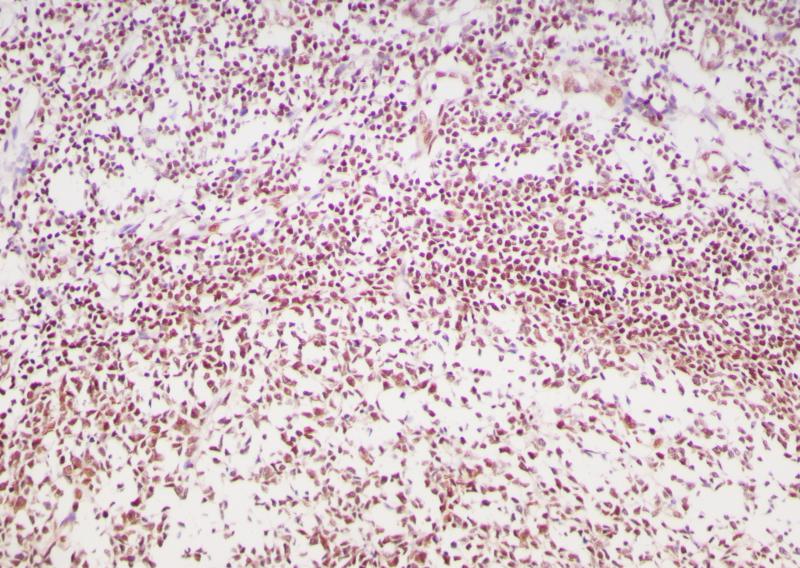

阑尾MGMT(BP6217)染色

MGMT,O6 -甲基鸟嘌呤-DNA甲基转移酶,是一个DNA修复酶,参与对DNA中O6 -甲基鸟嘌呤(O6-MeG)生物效应的细胞防御。MGMT启动子甲基化将导致 MGMT基因的沉默,从而减少 MGMT mRNA和蛋白的表达,因此,患者的 MGMT基因启动子区甲基化程度越高,使用烷基化药物的效果可能越好。

亚细胞定位

细胞核